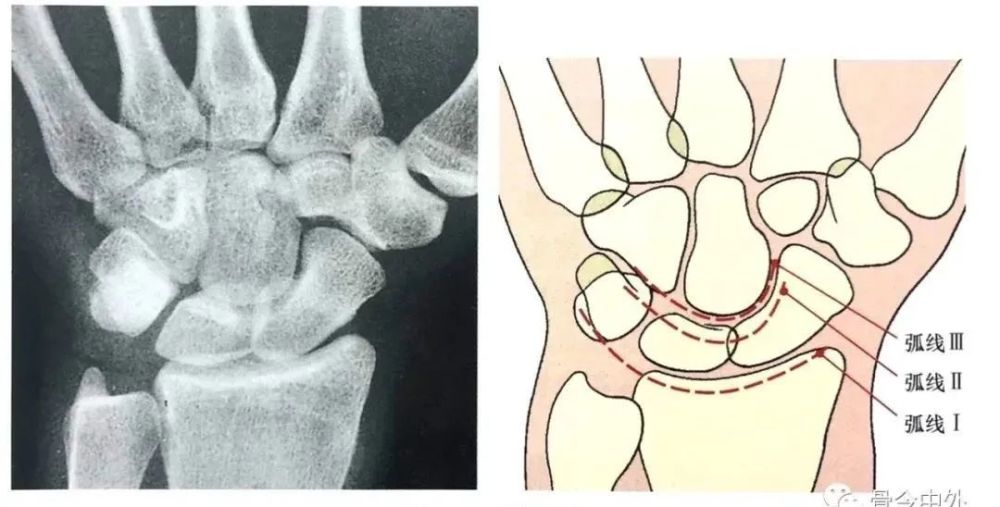

在正常腕关节背掌位x线片上3个平滑的弧线勾画出近侧列和远侧列腕骨.

在正常腕关节背掌位x线片上3个平滑的弧线勾画出近侧列和远侧列腕骨